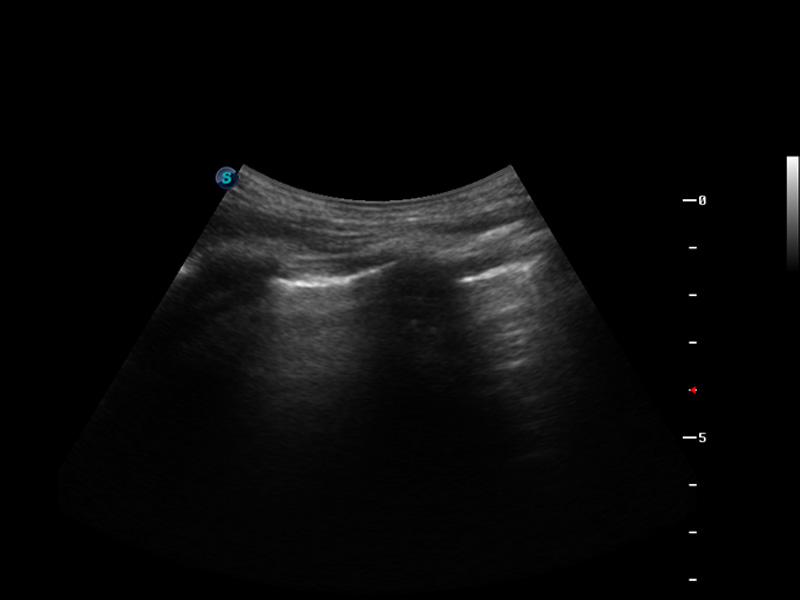

S9便携式彩色多普勒超声诊断仪是诸侯快讯官网研发的高端便携彩超设备,外观设计新颖、产品性能卓越。S9在便携超声领域采用了突破传统的触摸屏交互设计,并以先进的软件硬件技术和设计理念,为您带来清晰的图像质量、稳定的工作性能和便捷的操作体验。